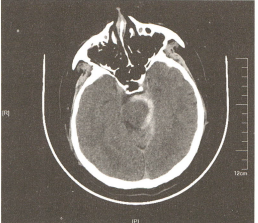

15%的患者运用数字减影血管造影(DSA)仍未发现明确的出血来源,根据出血位置,分为中脑周围非动脉瘤性蛛网膜下腔出血(perimesencephalicnon-aneurysmalsubarachnoid hemorrhage,PNSH)(图-1)和非中脑周围非动脉瘤性蛛网膜下腔出血(non-perimesencephalic non-aneurysmal subarachnoidhemorrhage)(图-2)。

图-1  中脑周围非动脉瘤性蛛网膜下腔出血

图-2非中脑周围非动脉瘤性蛛网膜下腔出血

1991年,Rinkel首先描述了PNSH的标准定义:出血的中心紧邻中脑的前方,伴有或不伴有向环池的基底部扩展的出血。未完全充满纵裂池的前部,一般不向侧裂池外侧扩展,且无明显的脑室内血肿。PNSH作为一种独立类型的SAH,约占SAH所有病因的10%左右,发病率为6/100万,在DSA为阴性结果的SAH患者中,PNSH约占其总数的21%~68%。结合患者起病缓慢,无意识障碍,预后良好,无再出血及脑缺血,邻近的视交叉池、脑实质及脑室内无出血,研究者们推测,PNSH的出血来源可能是静脉性出血或毛细血管渗血。另外,PNSH还包括两种特殊类型:①脑桥前池出血,出血常常仅位于脑桥前池,有时可向延髓前池蔓延;②四叠体池出血,出血位于四叠体池内,占PNSH总数的1/5。Rinkel等人所总结的PNSH影像学表现目前已成为临床公认的诊断标准:①PNSH的出血中心位于中脑前方的脑池,可延伸至环池前方或侧裂池的基底部;②前纵裂池或外侧裂池内可有少量的血液充盈,但不完全充盈;③无明显的脑室内出血。